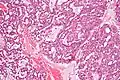

Polymorphous low-grade adenocarcinoma. H&E stain.

Micrograph of a polymorphous low-grade adenocarcinoma. H&E stain.

PLGAs consist of a monomorphous cell population that has a varied histologic morphology.

Microscopically, its histology can be confused with an adenoid cystic carcinoma and a pleomorphic adenoma.